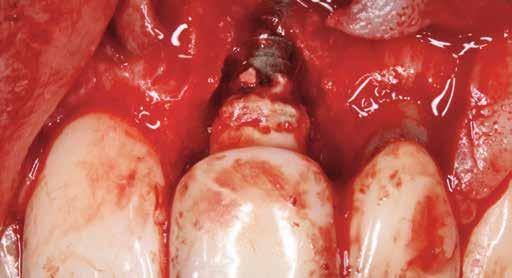

A sebészeti eljárás

Mind a hat implantátum esetén kétlépcsős műtétet végeztünk. Minden sebészeti eljárást bódítás, illetve preoperatív szisztémás antibiotikus terápia nélkül végeztünk. A négy eset közül kettőnél leukocitában és vérlemezkében gazdag fibrint (L-PRF) alkalmaztunk a beavatkozás során (IntraSpin, BioHorizons; 2. táblázat). Minden esetben a pontos CERALOG menetvágási (maximum 15 ford./perc) és fúrási (maximális fúrási fordulatszám: 550–800 ford./perc) protokollt követtük. Az összes implantátumot manuálisan helyeztük be 35 Ncm maximális nyomatékkal. Az implantátumokba PEEK zárócsavar került (2. ábra). A lágyszövetet atraumatikus, felszívódó varrattal, szorosan zártuk/összevarrtuk. A műtétek után szövődmények nem jelentkeztek. A pácienseket arra kértük, hogy a műtét utáni héten naponta kétszer öblögessenek klórhexidinnel (PERIO-AID, 0,05%, DENTAID). Az alsó állcsontnál három hónapos, a felső állcsontnál öt hónapos gyógyulási időt vettünk figyelembe. Három hónap (1. eset) és öt hónap (2., 3. és 4. eset) elteltével a műtétek második stádiumát helyi érzéstelenítés mellett végeztük. A gyógyu-

lási csavarokat (PEEK titáncsavarral) maximum 15 Ncm-rel húztuk meg (3–6. ábra). Az összes implantátum kiváló stabilitást mutatott (a mérésekhez Periotestet használtunk, a Medizintechnik Gulden jóvoltából), és teljesen osszeointegrálódott. Ezt a radiológiai vizsgálatok is megerősítették.

2a 3a 4a 2b 3b 4b 2c 2d Pozíció Implantátum átmérő Implantátum hossz L-PRF Behelyezési nyomaték Eset 1 #35 4 mm 12 mm Nem 35 Ncm Eset 2 #25 4 mm 12 mm Nem 30 Ncm #26 4 mm 8 mm Nem 25 Ncm Eset 3 #16 4 mm 8 mm Igen 25 Ncm #26 4 mm 10 mm Igen 30 Ncm Eset 4 #26 4 mm 10 mm Igen 30 Ncm

2. a–d ábra: PEEK zárócsavarok az implantátumokba helyezve, 1. eset (a). 2. eset (b). 3. eset (c), 4. eset (d). 3. a–b ábra: Röntgenfelvételek három hónap után (a) és a gyógyulási csavarok behelyezve (b, 1. eset). 4. a–b ábra: Röntgenfelvételek öt hónappal később (a) és a gyógyulási csavarok behelyezve (b, 2. eset). 2. táblázat: Az implantátum tulajdonságai.